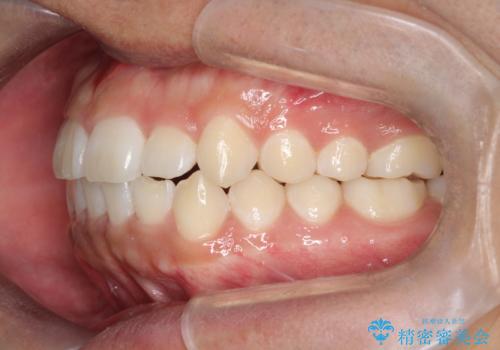

- 前歯のがたつきを主訴に来院されました。

上顎の前から2番目の歯の噛み合わせが反対になっていました。

抜歯矯正も考えられるケースでしたが、非抜歯での矯正を希望され、インビザラインにて治療することとなりました。

目立たずに矯正を終えることができ、患者様にも満足していただきました。